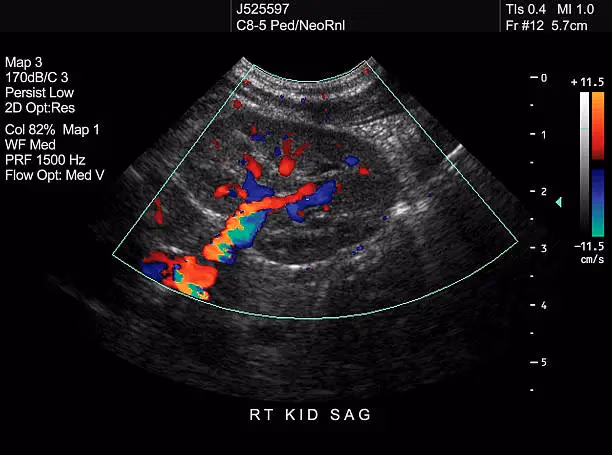

State-of-the-art diagnostic tools

Using modern imaging technology and advanced diagnostic methods ensures clearer scans and better insights. This allows for early detection and more reliable medical evaluations.

State-of-the-Art Ultrasound and Diagnostic Tools